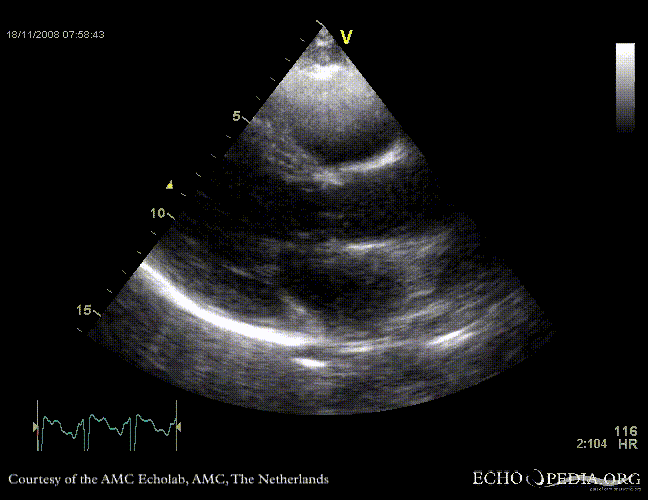

Rupture of the ventricular septum

VSR 1